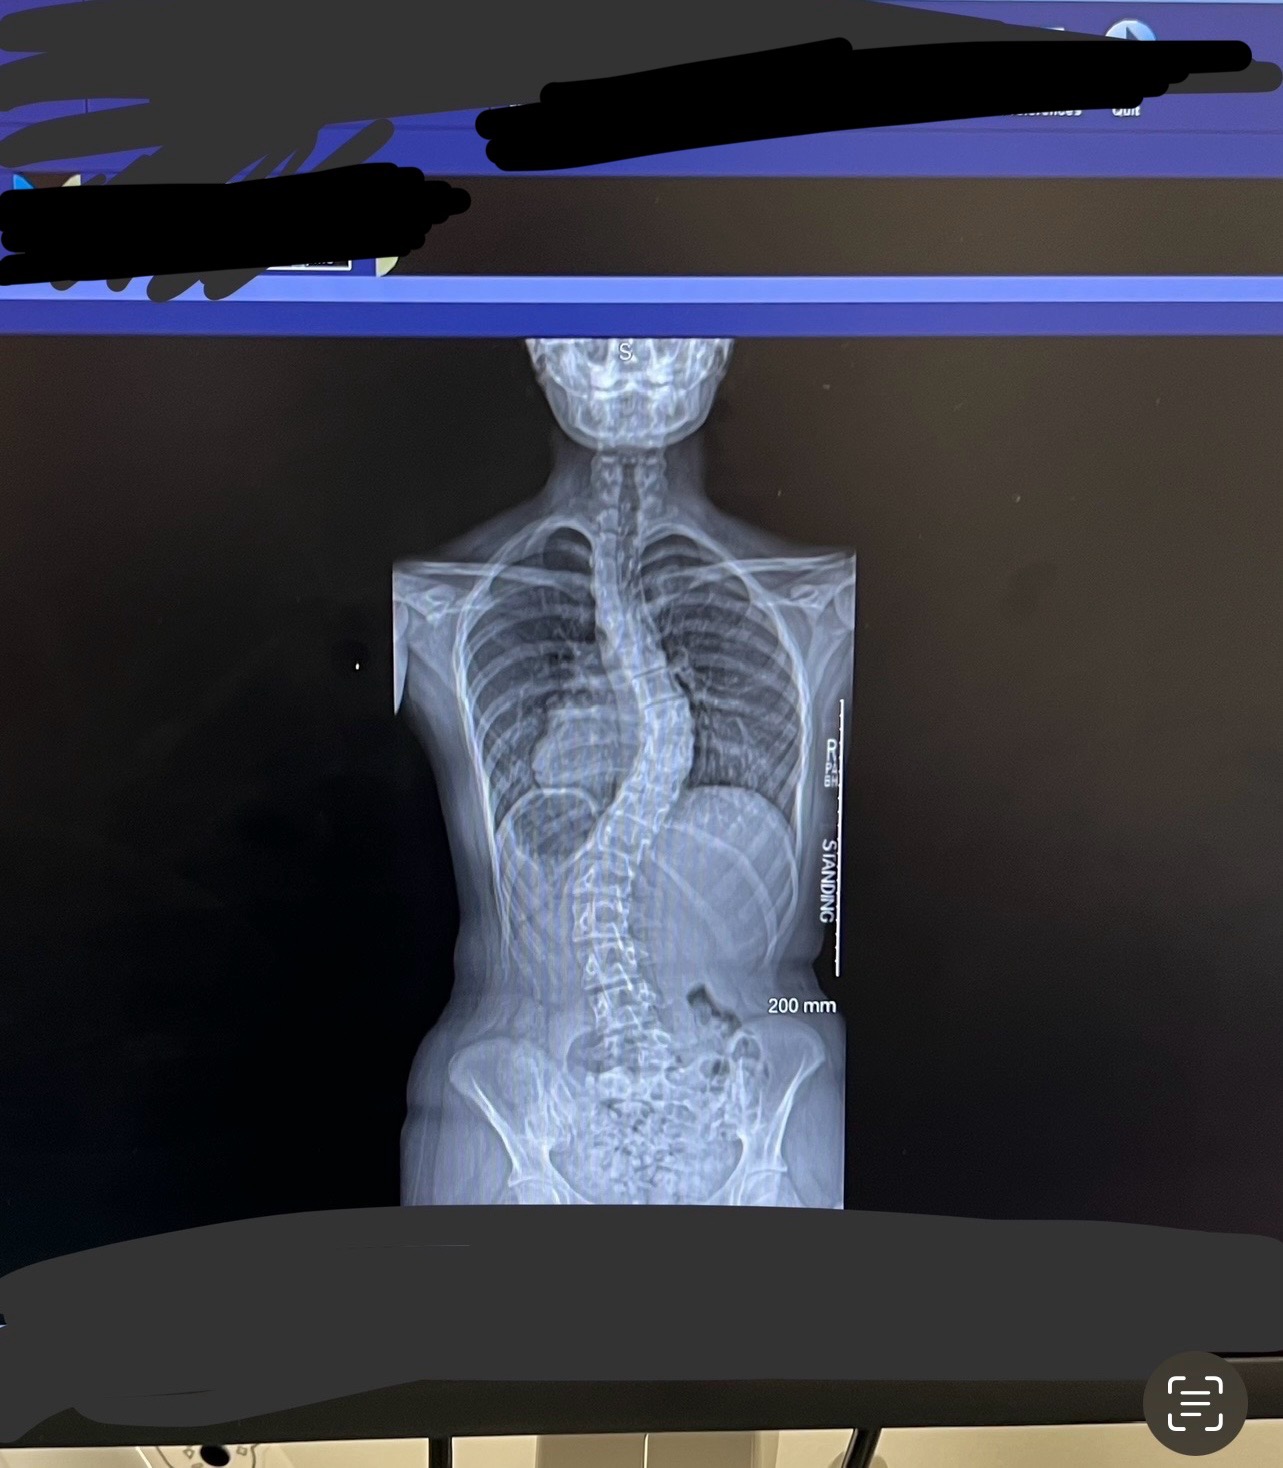

Her youngest, Lucy, has suffered for years from different symptoms, including scoliosis and pectus excavatum (her chest cavity is literally caving in, causing pressure on her heart.) After years of doctor visits, tests, and body braces, she was finally referred to a specialist at Children’s in Cincinnati, where they pinpointed that everything she has suffered through relates to this disease.